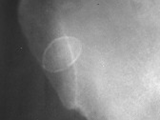

Plasmacytoma

Plasmacytoma